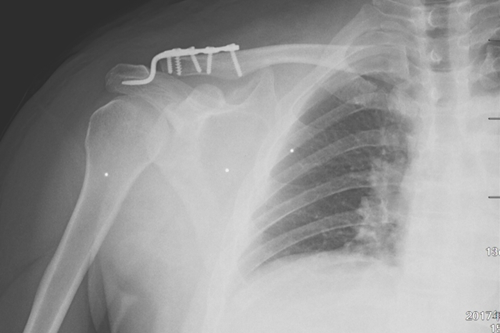

术后DR